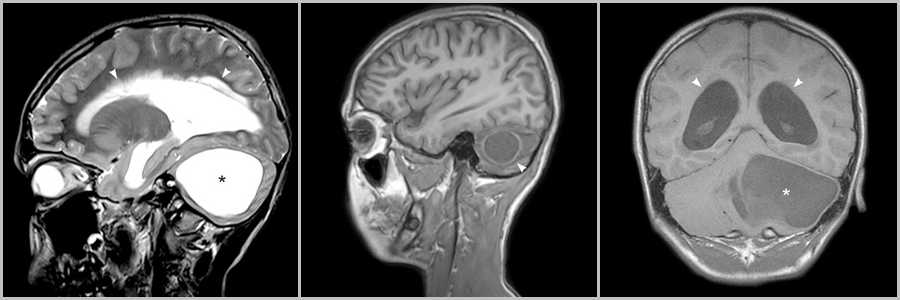

Киста с узлом более характерна для инфратенториальной локализации опухоли, а солидное образование для супратенториальной.

Рис.4

Опухолевая киста в гемисфере мозжечка (звёздочки на рис.4 и головка стрелки на рис.4), приводящая к сужению IV желудочка и вызывающая окклюзионную гидроцефалию с расширением желудочковой системы (головки стрелок на рис.4).

При локализации в задней черепной ямке (60%) опухоль может происходить в любом месте мозжечка – из полушария или червя .